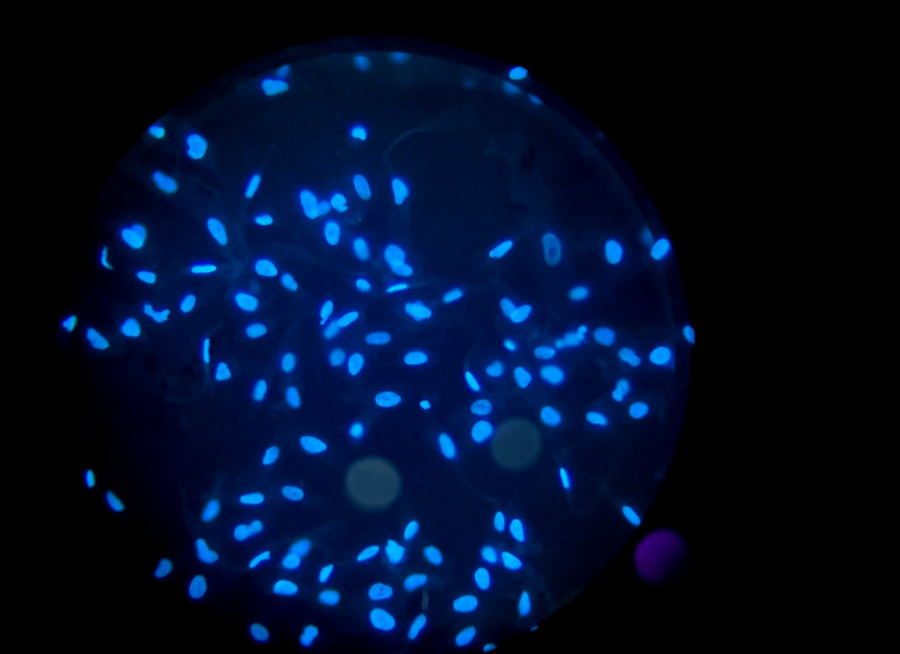

荧光显微镜相比普通光学显微镜有高特异性、高灵敏度等优势,是现代实验室必不可少的工具,而使用荧光显微镜成像拍照,怕的就是出现高强度的荧光染色背景,因为这会降低成像信噪比,导致样品信号不清晰、细节丢失。那么荧光染色背景太强有哪些成因呢?又如何避免呢?

一、环境光导致的背景荧光 二、透射聚光镜导致的背景荧光 三、来自样品、器皿和介质的背景荧光